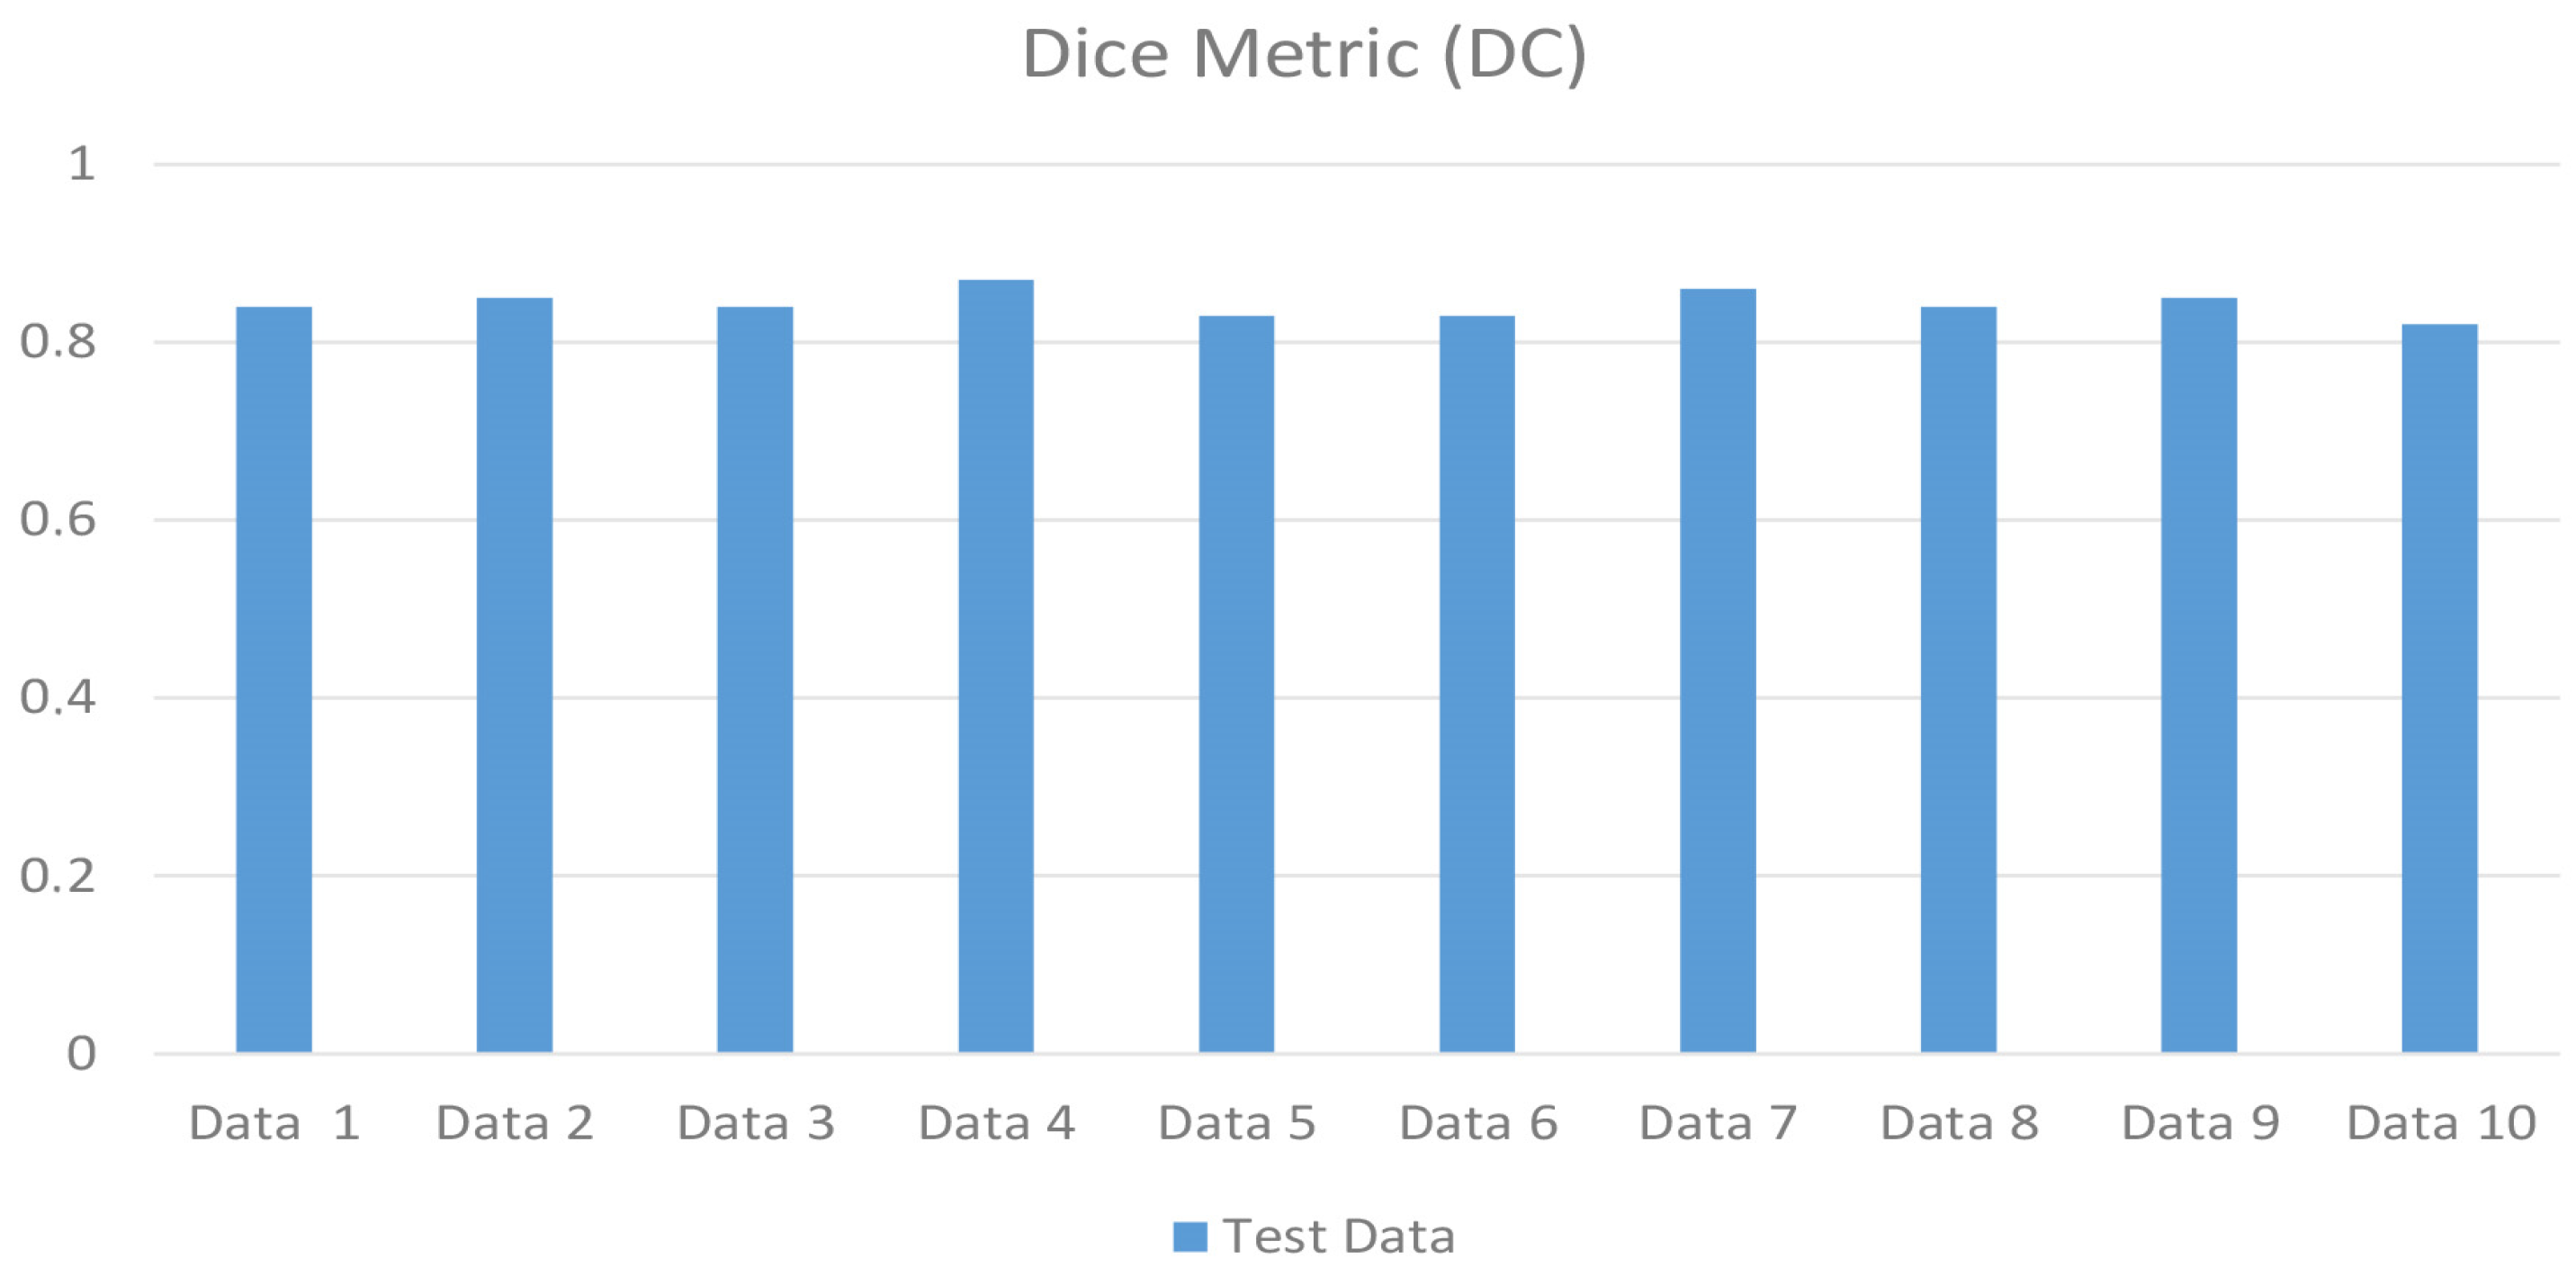

3. Results

| Metrics | Metric Formula | Metric Value |

|---|---|---|

| True Positive | 16,297.7 | |

| False Positive | 4214.2 | |

| False Negative | 1624.5 | |

| Precision | TP/(TP + FP) | 0.7888 |

| Recall (Sensitivity) | TP/(TP + FN) | 0.9168 |

| Dice Coefficients (DC) | (2 × T P)/(2 × T P + F P + F N) | 0.8465 |

| Intersection over Union (IoU) | (|A∩B|)/(|A∪B|) | 0.7341 |

| F1-Score | 2 × (Precision × Recall)/(Precision + Recall) | 0.8480 |

| 95% Hausdorff Distance (95%HD) mm | dH95(A, B) = max(d95(A, B), d95(A, B)) | 0.9460 |